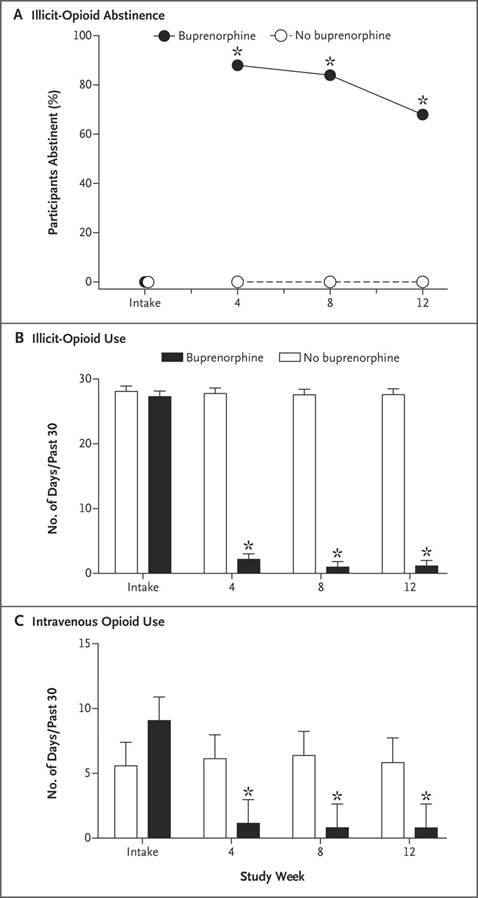

Correspondence: Interim Buprenorphine vs. Waiting List for

#Opioid Dependence http://nej.md/2h8fMsj pic.twitter.com/aYc27LorA8